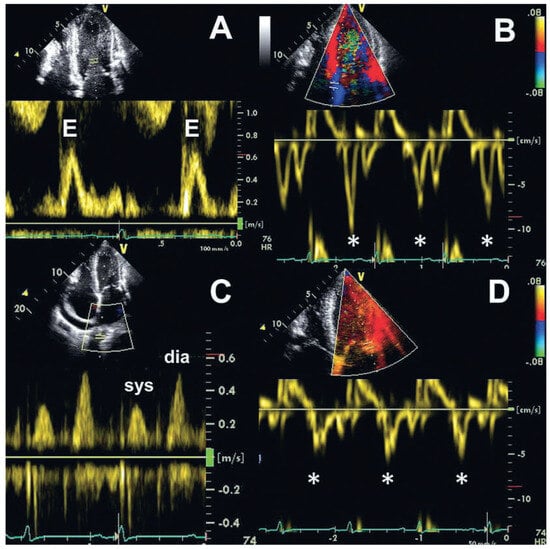

A 56-year-old man was admitted with massive signs of right heart failure, which had evolved over weeks. Chest X-ray revealed extensive pericardial calcifications in the lateral view ( Figure 1). Transthoracic echocardiography showed only mildly impaired biventricular systolic function but a dilated inferior vena cava without respiratory variability. The peak early mitral annular velocities (e’) assessed by pulsed wave tissue Doppler at the septal and lateral mitral annulus were 8 and 6 cm/s, and the ratio of the peak early transmitral velocity (E) to e’ (E/e’), based on an average e’ of 7 cm/s, was only 10 (Figure 2A,B,D). The pulmonary venous flow was clearly abnormal however (Figure 2C). There was an exaggerated respiratory variability of mitral in-flow (Figure 3).

Figure 2. Transthoracic Doppler echocardiography. (A) Transmitral inflow assessed by pulsed wave Doppler (peak early transmitral velocity [E], 0.7 m/s). (B,D) Pulsed wave tissue Doppler at the septal (B) and lateral (D) mitral annulus revealing preserved peak early mitral annular velocities (e’, asterisks; septal 8 cm/s, lateral 6 cm/s). (C) Pulmonary venous flow assessed by pulsed wave Doppler showing prominent diastolic flow. dia = diastolic; sys = systolic.